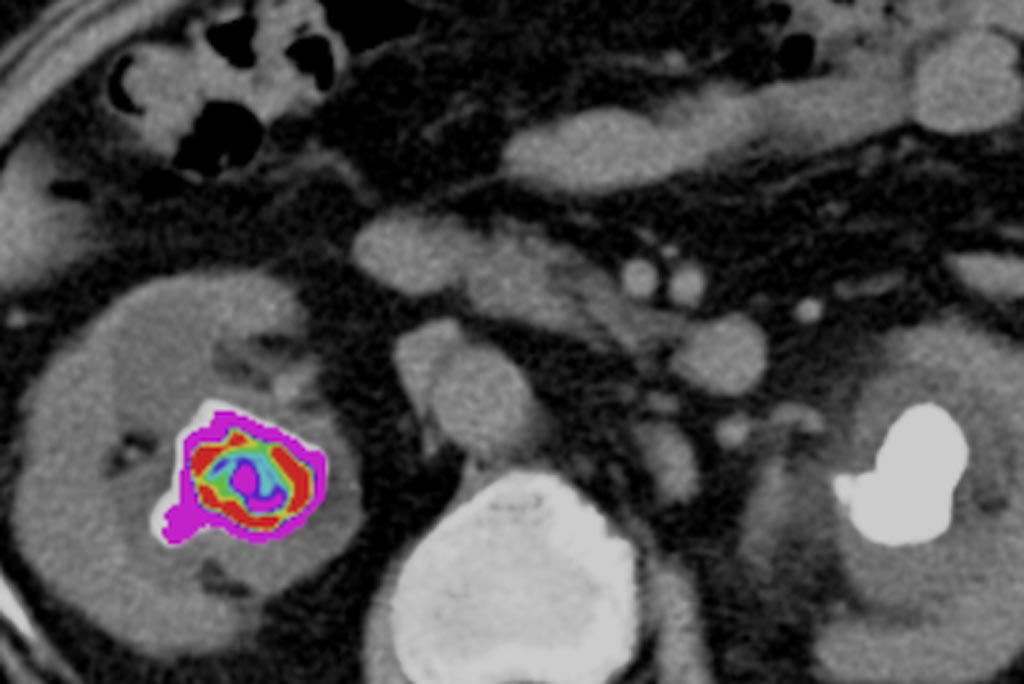

Британская компания StoneChecker выпустила решение, предназначенного для анализа камней в почках. Программное обеспечение использует медицинские изображения (сканы, полученные при помощи компьютерной томографии) и проводит детальный анализ камней в почках, что позволяет врачам получить критически важную информацию, чтобы определить наиболее эффективное лечение для каждого конкретного пациента.

Система использует специализированный алгоритм для того, чтобы изучить гетерогенность камня и его текстуру, которая невидима в стандартных условиях. В итоге врачи получают справку, в которой отражены физические характеристики камня, такие как объем камня, его средняя структурная плотность, расстояние от камня до кожи, его асимметрия и т.д.

Этот программный продукт уже получил разрешение на использование в странах Европейского Союза.